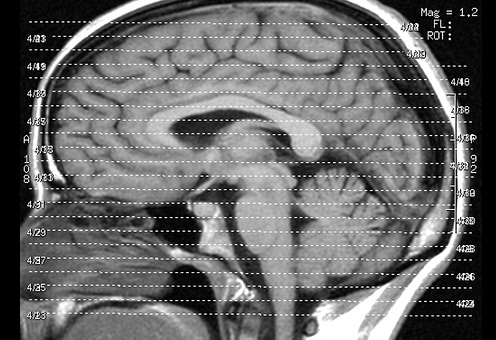

Sowohl gestresste als auch nicht gestresste Probanden lernten, das Wetter anhand der Symbole vorherzusagen. Nicht gestresste Teilnehmer konzentrierten sich dabei auf einzelne Symbole und nicht auf Symbolkombinationen. Sie verfolgten also bewusst eine einfache Strategie. Die Kernspin-Daten ergaben, dass sie dafür bevorzugt eine Hirnregion im mittleren Schläfenlappen aktivierten – den Hippocampus, der für das Langzeitgedächtnis wichtig ist. Gestresste Probanden wandten hingegen eine komplexere Strategie an. Sie trafen ihre Entscheidung basierend auf Symbolkombinationen. Das taten sie jedoch unbewusst, das heißt, sie konnten ihre Strategie nicht in Worte fassen. Passend dazu zeigten die Hirnscans: Bei gestressten Probanden war das sogenannte Striatum im Mittelhirn aktiviert – eine Hirnregion, die für eher unbewusstes Lernen verantwortlich ist. „Stress stört das bewusste, zielgerichtete Lernen, das vom Hippocampus abhängt“, folgert Lars Schwabe. „Also nutzt das Gehirn andere Ressourcen. Bei Stress kontrolliert das Striatum das Verhalten – das rettet die Lernleistung.“ nin